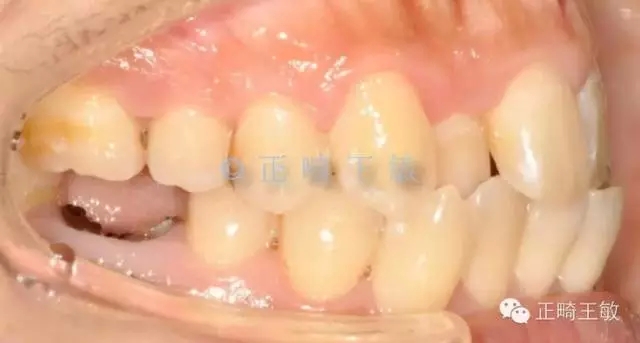

有了一個目標后,矯正就很簡單了,拔掉一顆牙,7個月順利讓牙齒移動到我們想要的位置:

雖然這個時候正畸并沒有結束,但對于種植來說,間隙和排列,已經足夠了,畢竟種植周期也要4個月,后面的治療就是繼續(xù)關閉間隙,調整咬合,同時等著那顆種植牙生根發(fā)芽。來看看最終的樣子: